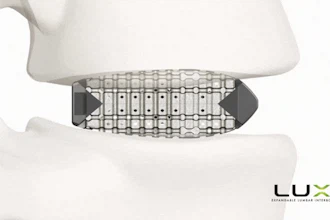

When designing an implantable device, the primary goals are functionality, durability, and minimal invasiveness. The IOP-Connect™ sensor, which measures just 4mm in length and 1.5mm in diameter, is specifically engineered to continuously monitor the pressure inside the eye, critical for patients suffering from glaucoma.

- Miniaturization: Implantable devices must be small enough to minimize trauma during implantation and avoid interfering with the body's normal functions. IOP-Connect's small form factor—achieved through advanced microfabrication techniques—ensures minimal invasiveness. This is particularly critical for ocular implants where space is limited, and precision is key. The miniaturization is enabled by leveraging silicon-based pressure sensing technology, which allows for precise, accurate measurements of absolute pressure while maintaining a small footprint, essential for integration within the eye's delicate structures.

- Environmental Durability: Implantable sensors must be durable enough to withstand the body's constant physiological changes. It was imperative to ensure the sensor's housing was resistant to bodily fluids, temperature fluctuations, and potential chemical interactions in the eye. The materials used were carefully selected to prevent any adverse reactions, in line with ISO 10993 biocompatibility standards. The external housing of the sensor is crafted from biocompatible materials such as titanium and medical-grade polymers, which offer corrosion- and degradation-resistance within the aqueous environment of the eye.

- Component Integration: Integrating multiple components, such as the sensor and the external reader system, requires careful coordination. Injectsense's reader uses both digital and analog systems, which must be compatible regarding power consumption and data transmission. We designed the PCB for the external reader and system, ensuring it could communicate wirelessly with the implanted sensor while maintaining an efficient power profile. We also considered the optimal distance between the sensor and the reader—currently an inch and a half—enabling reliable data transmission from within the eye to an external device. The sensor also incorporates MEMS (Micro-Electromechanical Systems) technology, which allows for precise, low-power, and reliable pressure measurements with a minimal footprint.